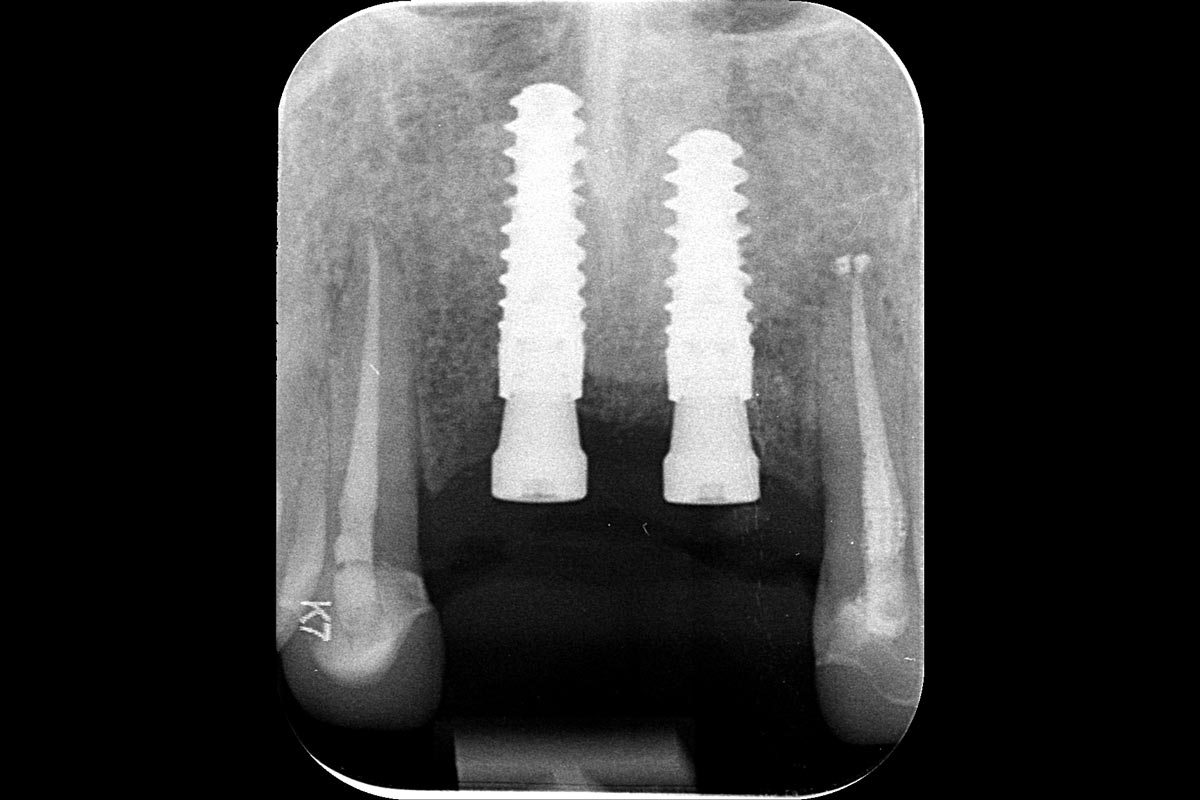

25/26 - X-ray scan at implant installation 6 months after augmentation

Ridge augmentation in the maxilla with maxgraft® bonebuilder in the aesthetic zone - Dr. M. Kristensen